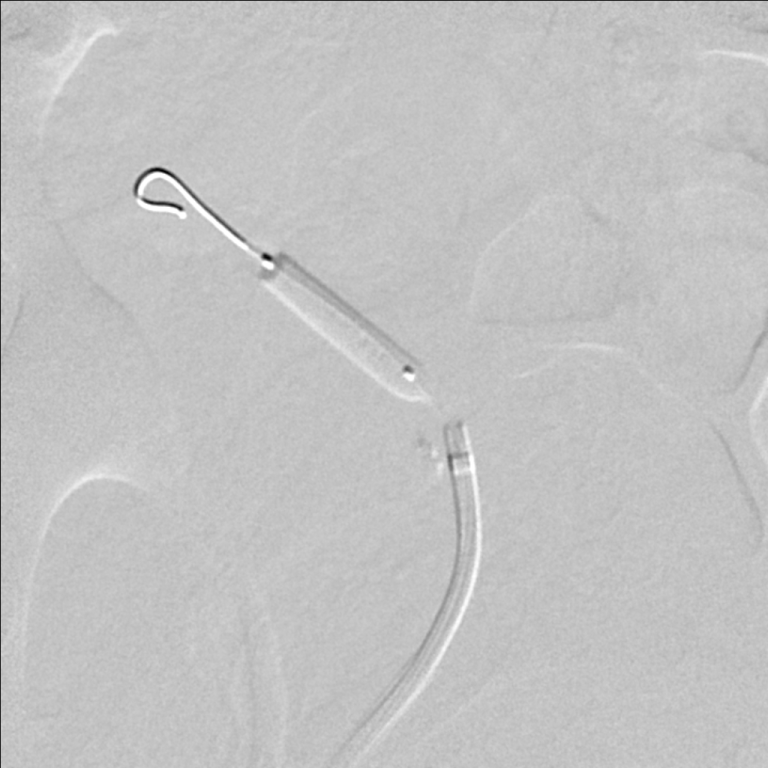

The patient was referred for renal angiography, which revealed a focal web-like stenosis in the mid portion of the transplanted renal artery (Figure 1). A Fractional Flow Reserve (FFR) wire was advanced through the stenosis and a 45 mmHg gradient was noted across the lesion. Subsequently, a 5 × 20 mm RX Viatrac 14 Plus balloon (Abbott Vascular, Inc., CA, US) was crossed and inflated to its nominal pressure (Figure 2). Post-angioplasty (Figure 3), the systolic gradient across the stenosis decreased to 25 mmHg. More aggressive dilatations were not performed because of the proximity of the stenosis to the bifurcation of the renal artery. A decrease in the blood pressure was noted in the recovery room and remained controlled without antihypertensive therapy in the subsequent visits.

Figure 3: Selective angiography of the transplanted renal artery after transluminal angioplasty. View Figure 3